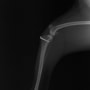

■ 症例24 キャバリア 7か月

左右膝蓋骨内方脱臼(左:グレードⅣ 右:グレードⅢ)

以前から左右後肢の跛行が認められ、整形外科学的検査・レントゲン検査により左右の膝蓋骨脱臼が認められた。症状が重度である左膝の膝蓋骨脱臼整復術を行った。外科手技は縫工筋及び内側広筋の解放、脛骨粗面の外側転位、滑車ブロック形造溝術、内外側関節方の縫縮を実施した。術後一か月時点で、左の膝蓋骨は安定しており経過は良好である。

本症例は成長期における重度の膝蓋骨脱臼であり、術後の再発の可能性もあるため、経過をしっかりと観察していく必要がある。また、今回手術を実施していない右膝に関しても経過を観察し、手術を検討していくこととする。